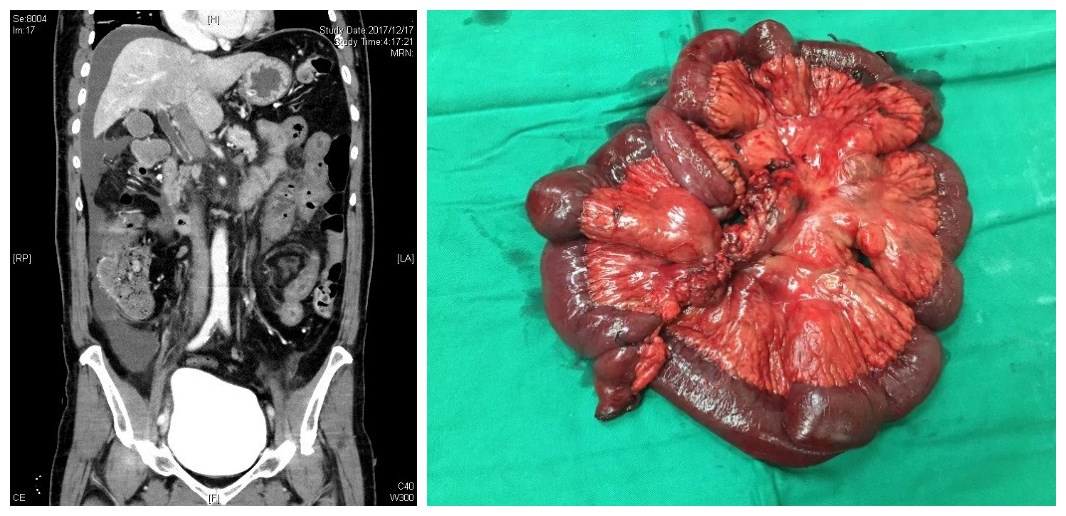

病例一:患者男,70岁,1个月来腹胀,间断全腹疼痛,10天来腹痛加重。于外院诊为肠梗阻,经禁食水、补液治疗后无缓解,来我院急诊。既往冠心病、房颤病史20年。经检查后发现门静脉及肠系膜静脉血栓形成,考虑存在肠坏死,遂行急诊手术。术中见2.2m小肠缺血,部分坏死,相应肠系膜静脉广泛血栓。予肠切除并由血管外科行肠系膜上静脉切开取栓治疗,将远近断端肠管分别提出腹壁并造瘘。术后患者经抗凝、补液抗炎治疗恢复良好,逐渐由胃肠外营养过渡到经回肠造瘘口灌注营养液。

病例二:女,45,近一周来腹痛,加重2天。于外院检查后考虑肠系膜上动脉血栓形成,转来我院进一步治疗。急诊腹部增强CT显示:腹腔干动脉、肠系膜上动脉栓塞,腹主动脉内长段漂浮血栓,急诊手术探查,肠管未见坏死,行肠系膜上动脉切开取栓+主动脉覆膜支架置入隔绝腹主动脉内血栓。术后筛查患者为遗传性抗凝血酶III缺乏症,运用利伐沙班抗凝,并逐渐由胃肠外营养恢复到肠内营养,病情稳定后出院,院外继续抗凝治疗。